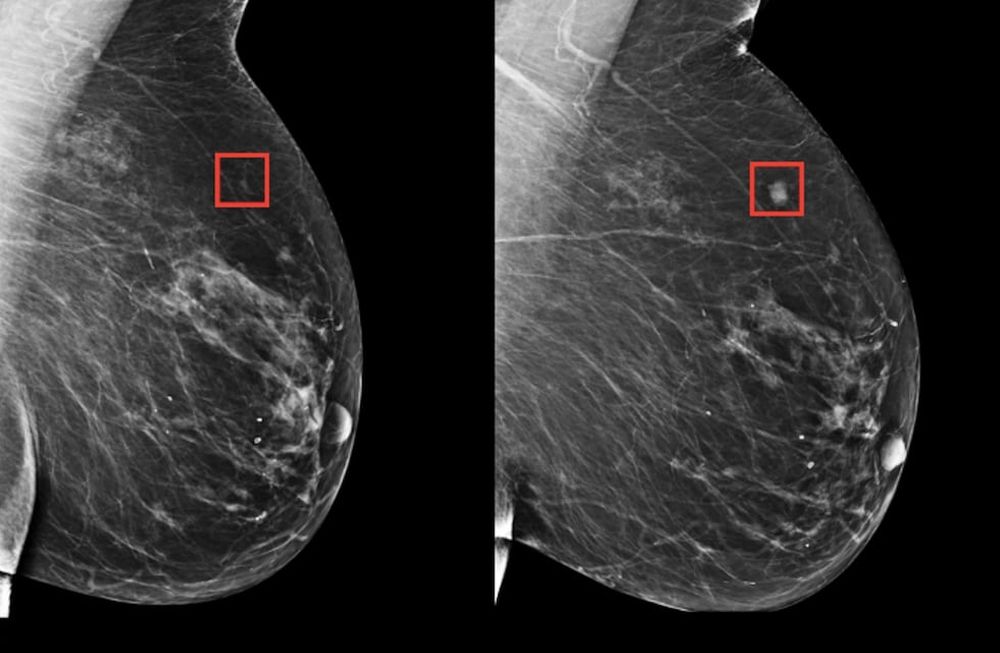

El mundo de la ciencia de la salud está revolucionado por un nuevo método basado en inteligencia artificial que permite detectar el cáncer de mama hasta 5 años antes de su desarrollo en el paciente. Se trata de un nuevo modelo de deep learning (aprendizaje profundo) que aplica algoritmos de IA a mamografías convencionales.

La identificación anticipada de los pacientes en riesgo a partir de este nuevo modelo de aprendizaje profundo se vuelve vital para detectar en una mamografía si el paciente desarrollará cáncer en el futuro.

Gracias a las mamografías y los resultados de más de 60.000 pacientes, los investigadores desarrollaron una serie de algoritmos que aprenden los sutiles patrones del tejido mamario que son precursores de un tumor maligno.

Así, en lugar de detectar de forma manual los patrones individuales, este modelo de aprendizaje profundo basado en la inteligencia artificial induce los patrones a partir de datos. Entrenado con más de 90.000 mamografías, este modelo detecta patrones tan sutiles que sería imposible reconocer con el ojo humano.